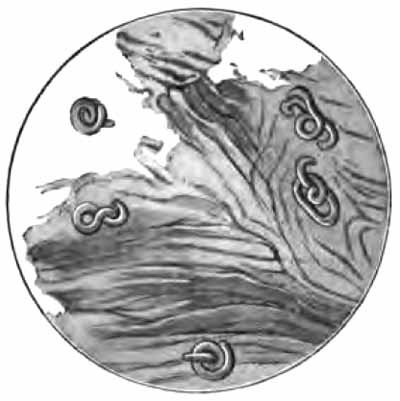

Curschmann's spirals

FIG. 5.—Curschmann's spirals: I., Natural size; II. and III., enlarged: a, central fiber (after Curschmann).

2. Curschmann's Spirals.—These peculiar structures are found most frequently in bronchial asthma, of which they are fairly characteristic. They may occasionally be met with in chronic bronchitis and other conditions. Their nature has not been definitely determined.

Macroscopically, they are whitish or yellow, twisted threads, frequently coiled into little balls (Fig. 5, I.). Their length is rarely over half an inch, though it sometimes exceeds two inches. Under a two-thirds objective they appear as mucous threads having a clear central fiber, about which are wound many fine fibrils (Fig. 5, II. and III.). Leukocytes are usually present within them, and sometimes Charcot-Leyden crystals. The central fiber is not always present.